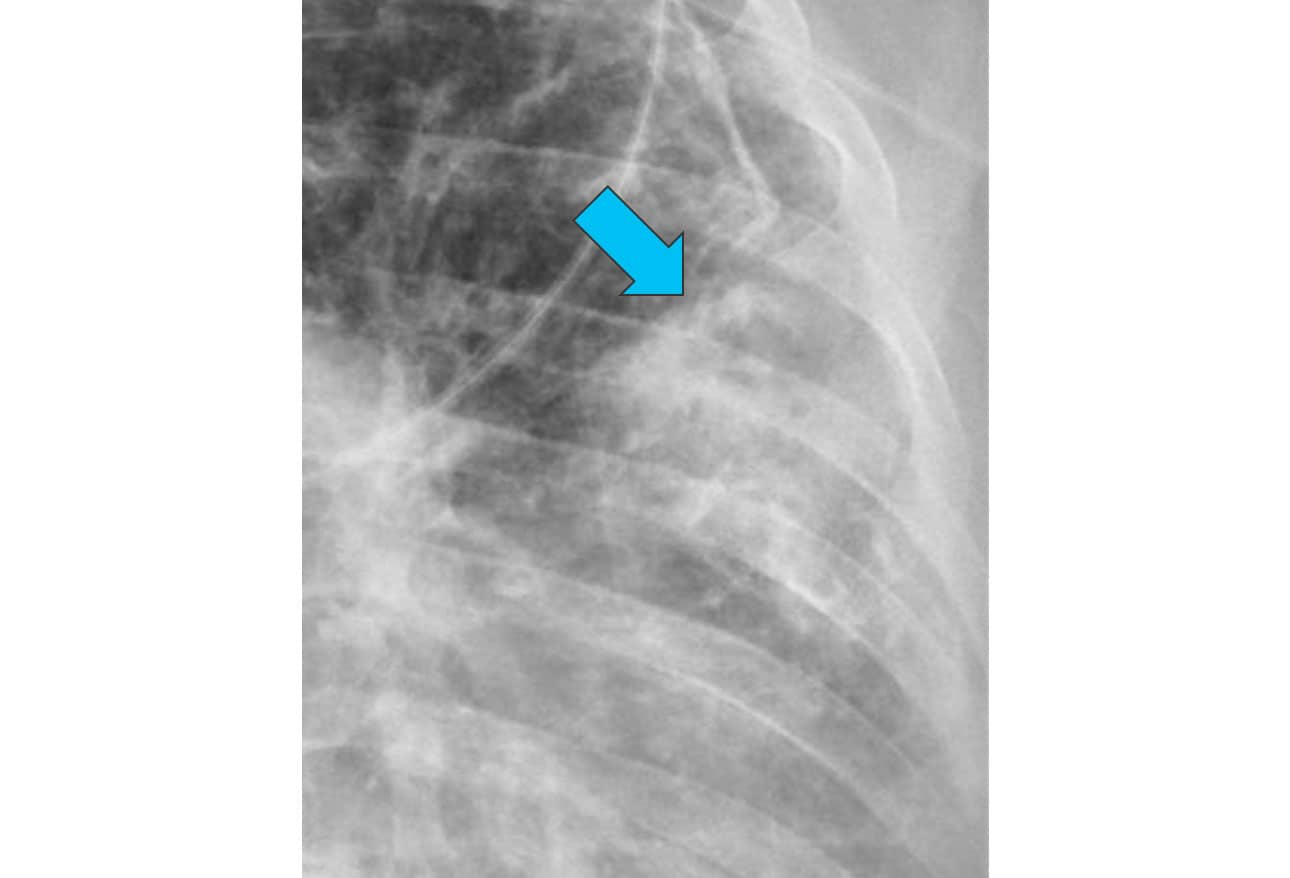

Chest XRays 16 Subtle But Key Findings You Need to Know

Chest XRays 16 Subtle But Key Findings You Need to Know Cap X Ray Findings It is ‘ atypical ’ with regard to resistance to beta. Web when clinical findings are suggestive of cap, blood test, various. Web for most patients with suspected cap, we obtain posteroanterior and lateral chest radiographs. Cap X Ray Findings.